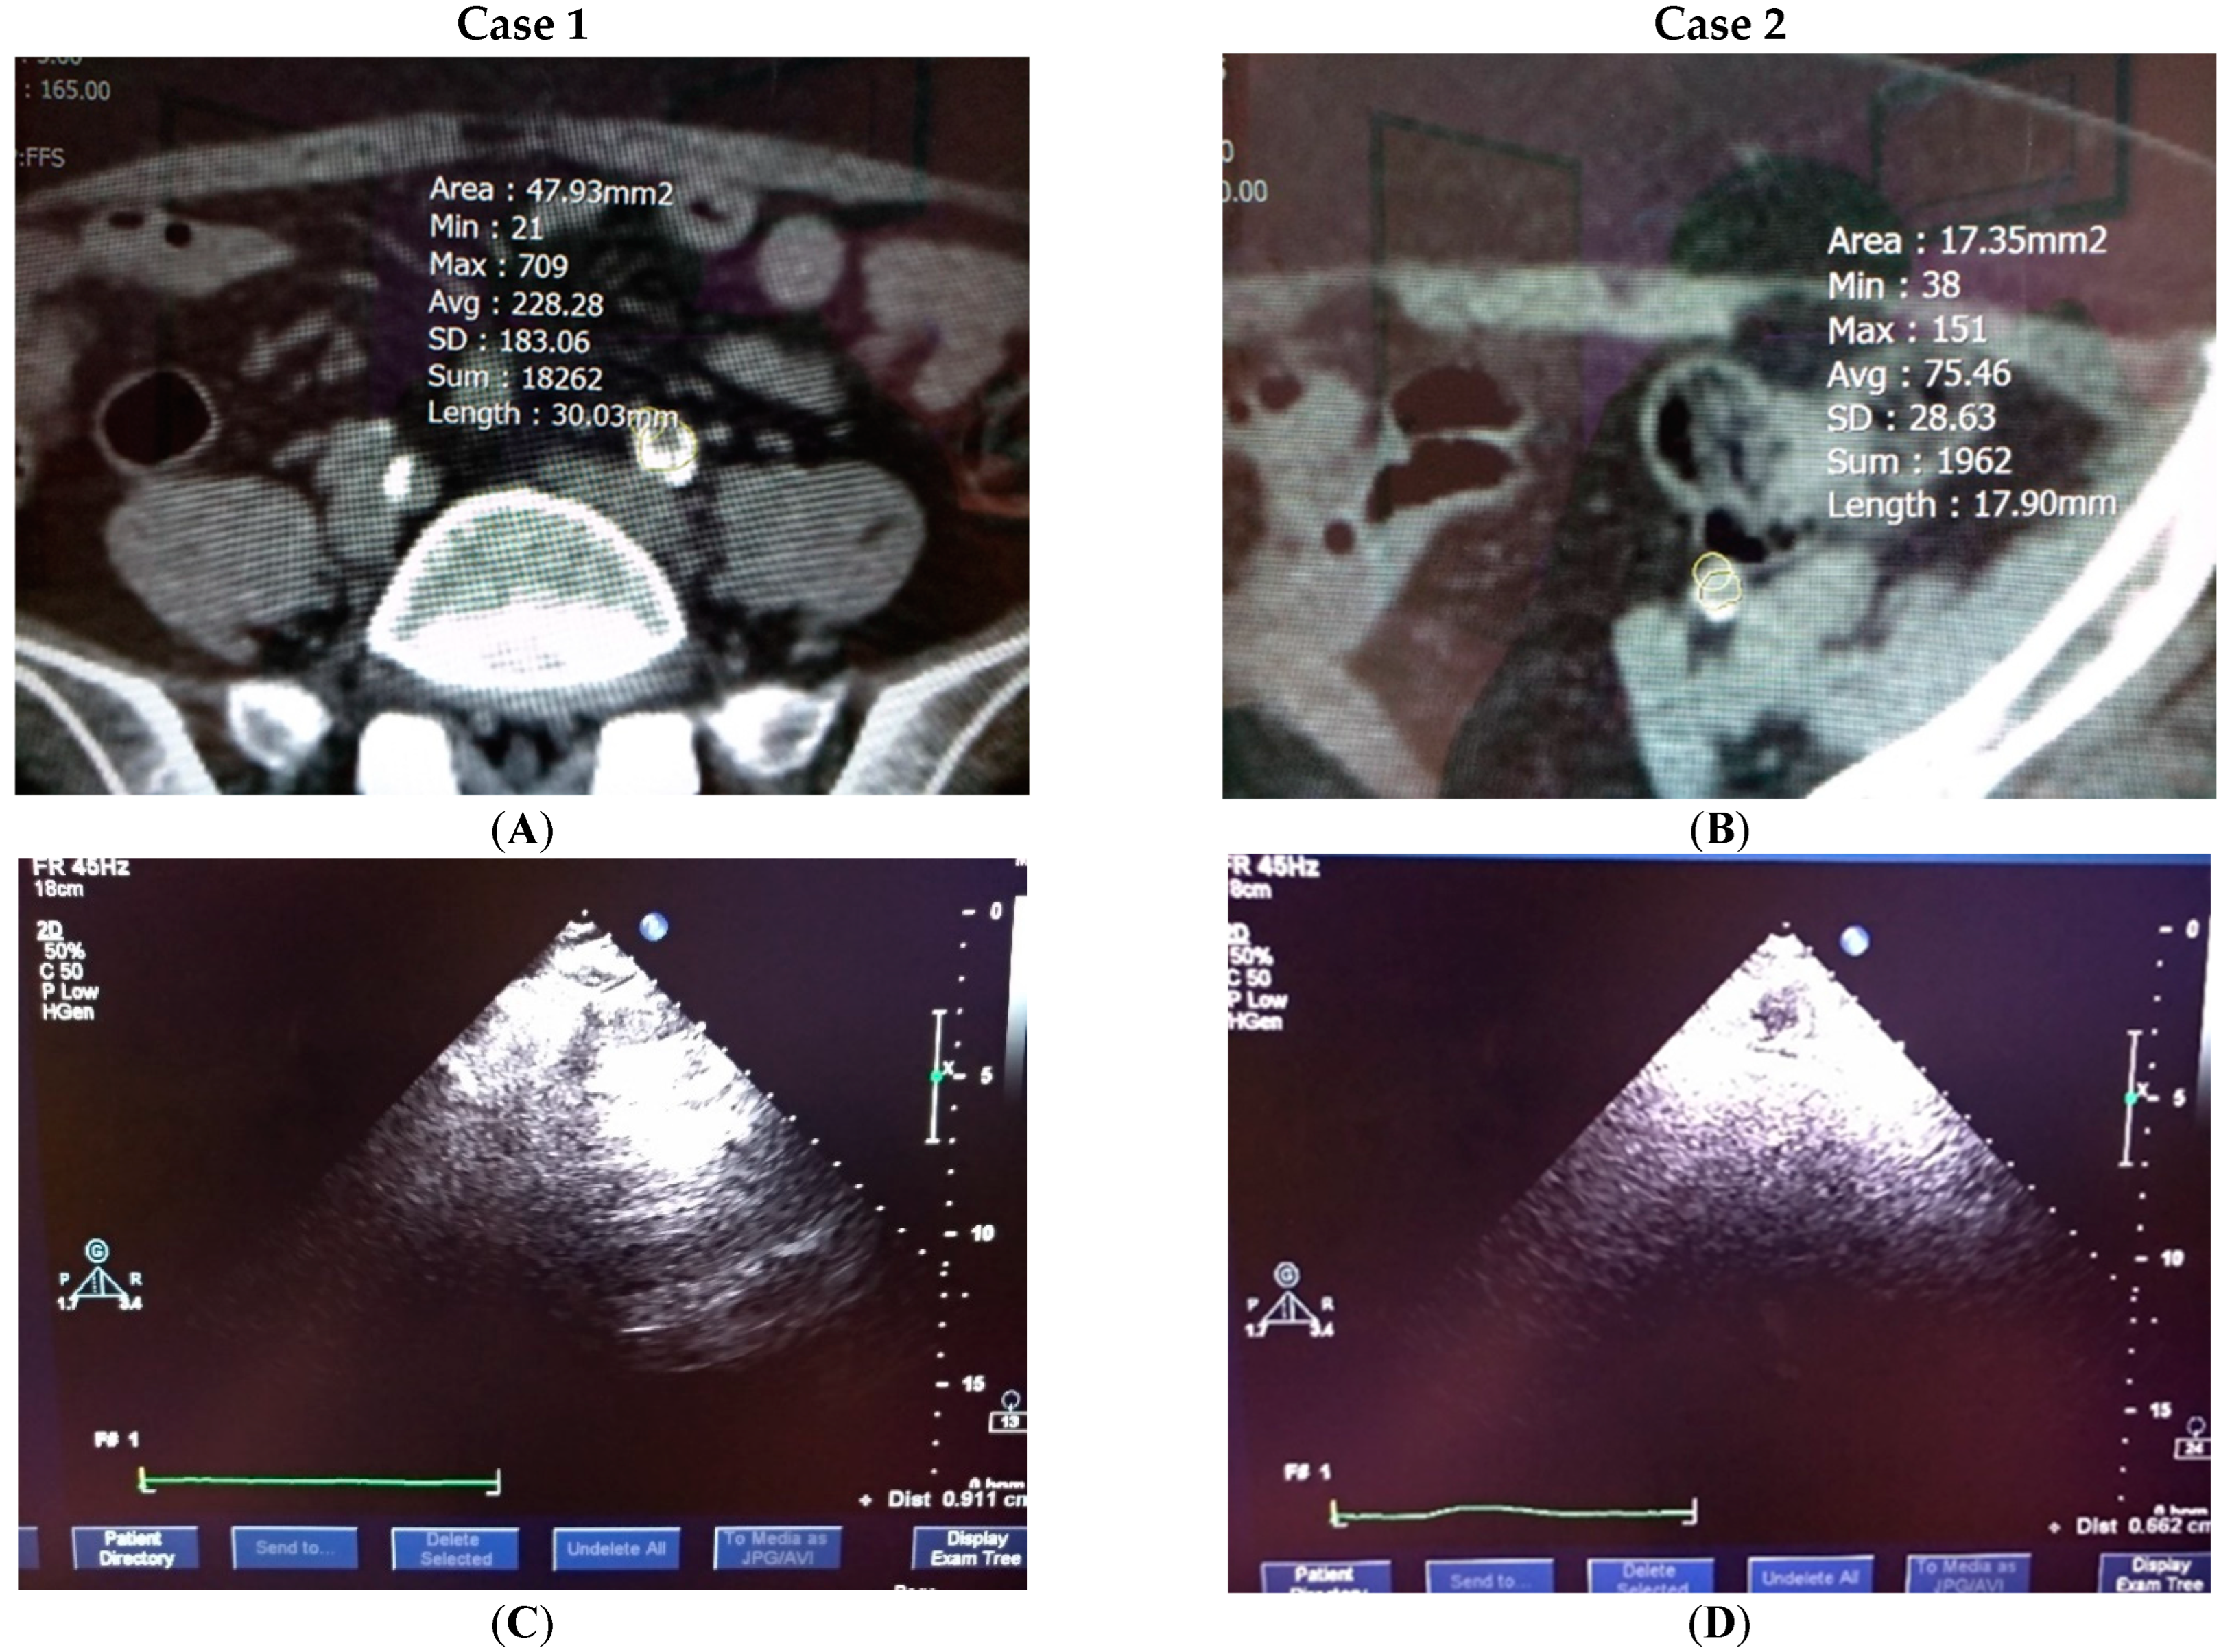

4.4. Clinical Testification